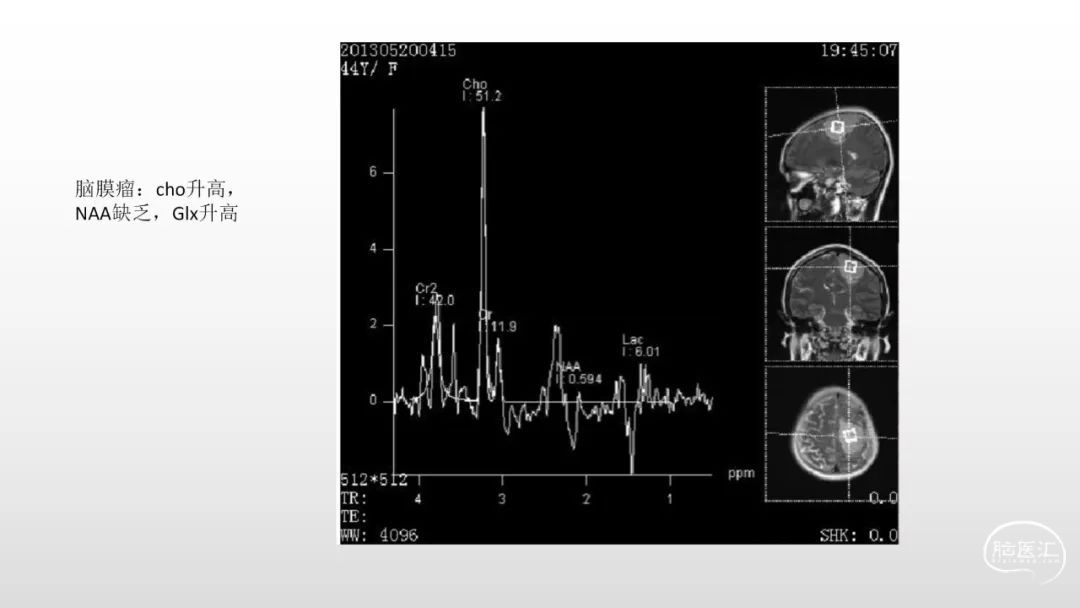

颅脑影像诊断基础知识讲座:脑膜病变